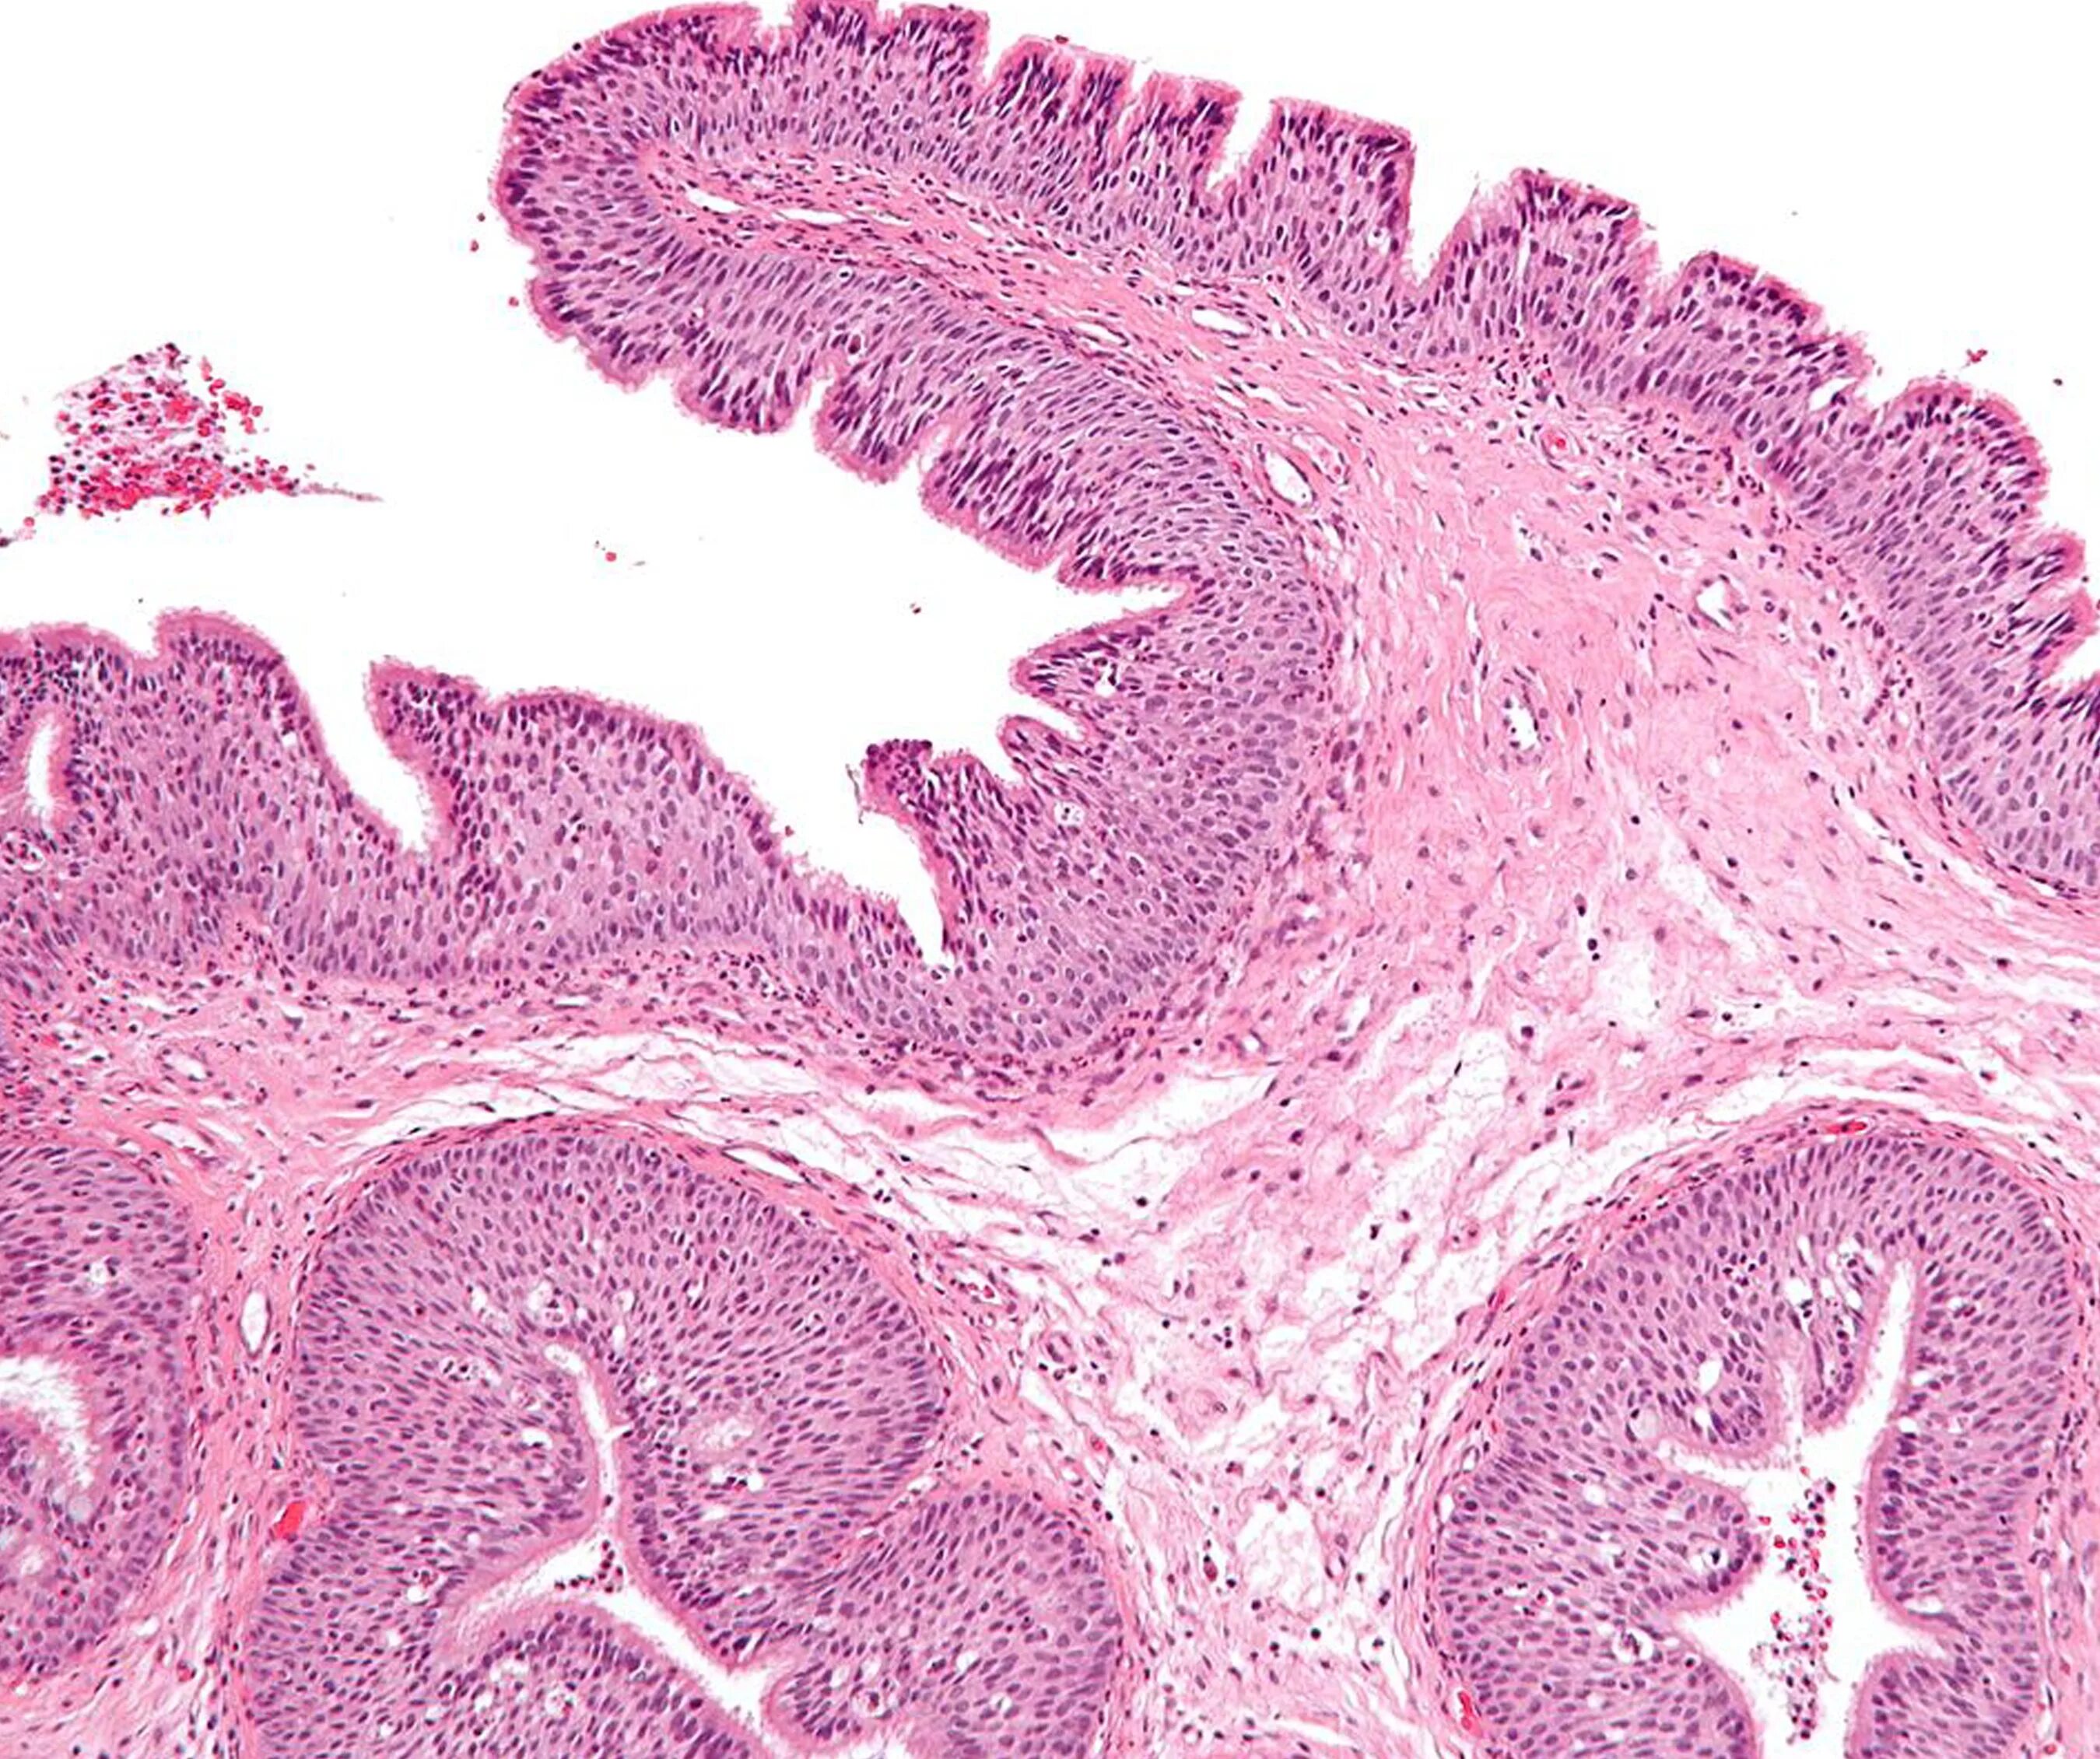

Папиллома гистология